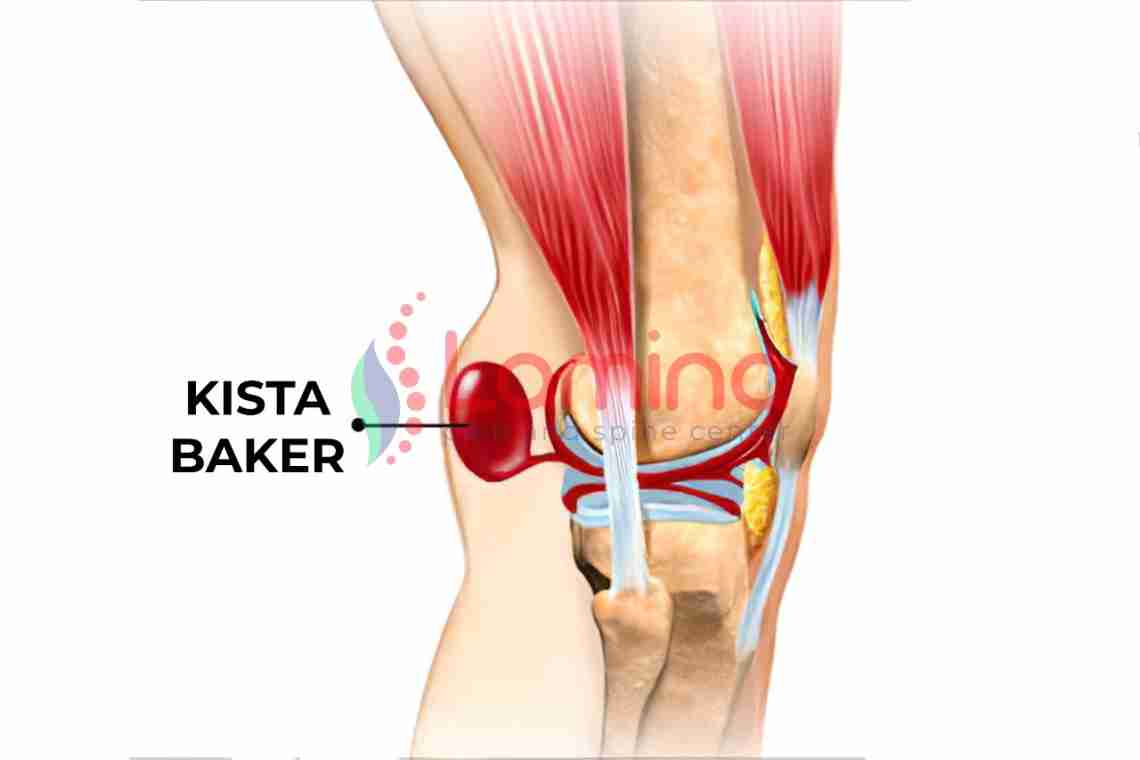

Фото и диагностика кисты Бейкера